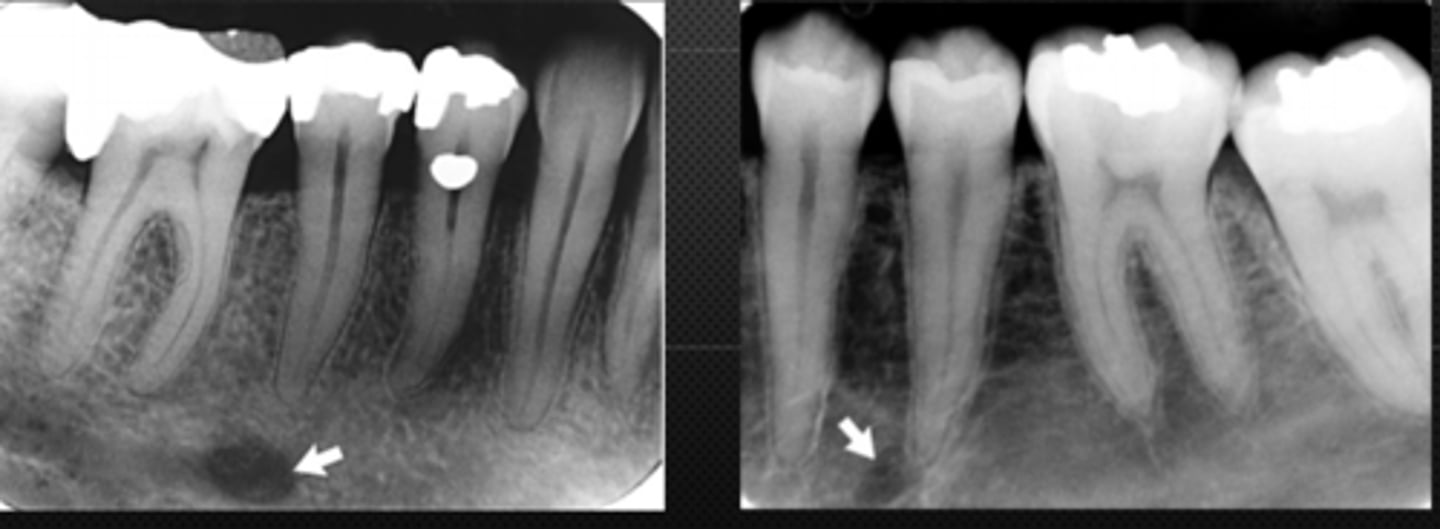

52

New cards

anterior border of the ramus

Name the structure the white arrow is pointing to.

<p>Name the structure the white arrow is pointing to.</p>

53

internal oblique ridge or mylohyoid ridge

Name structure the black arrow is pointing to.

<p>Name structure the black arrow is pointing to.</p>